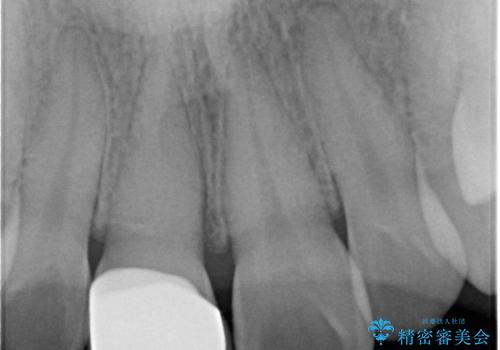

前歯の変色をキレイに セラミッククラウン審美治療

- 前歯の変色が気になる、見た目を改善したい!と審美性の回復を希望され来院されました。

ホワイトニングでは、周囲の歯との色調になじむほどには白くできないため、ジルコニアセラミッククラウンを用いて審美性を回復します。